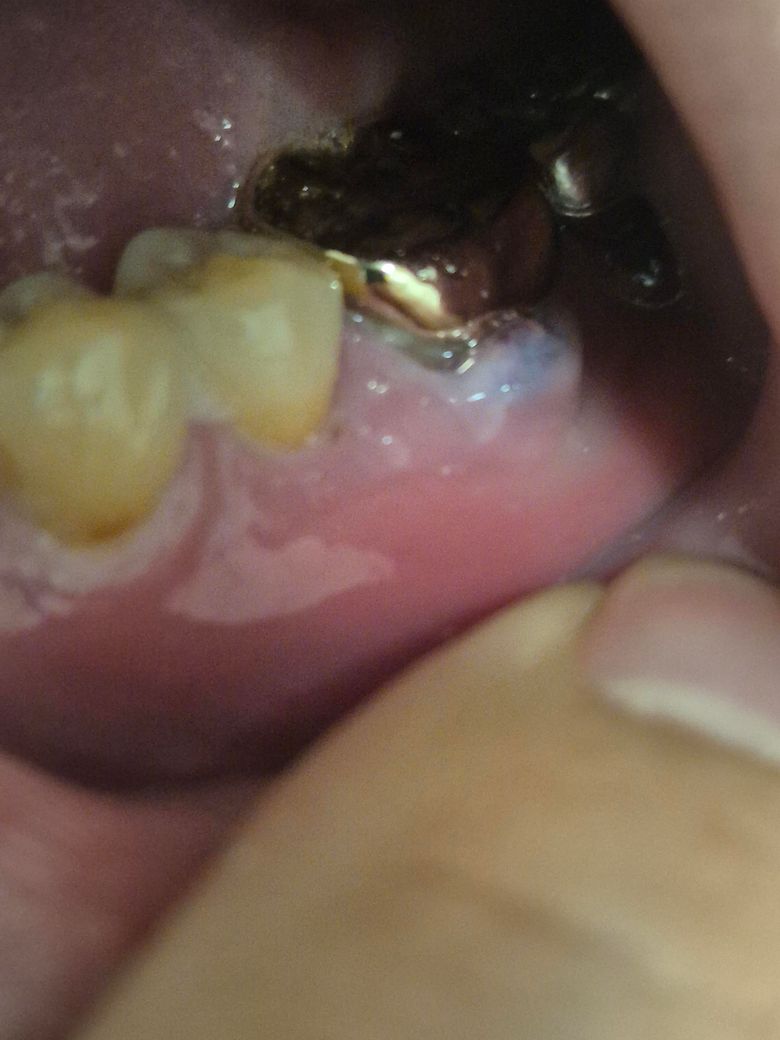

부은잇몸 질문이 있습니다 치과에 가니까

고름은 아니라 흰색으로 부어 있는데

• 1번 째 사진

이런 방식으로 치료하는 것이 기본입니다. 고름이 차서 동그랗게 부은 경우는 터트려 고름 빼는 절개 배농합니다. 재발하지 않게 하려면 그 부위에 음식물 잔사 안끼게 꼼꼼한 치솔질 하는 것입니다.

고름을 굳이 터뜨릴 필요 없습니다. 감염 우려 있고, 잇몸 재생에도 도움 안됩니다.

잇몸치료에 이어서 잇몸 수술 필요할 수도 있는 상황으로 보입니다.

잇몸에 염증등으로 인해서 붓기가 있다면 잇몸치료를 해야 합니다. 사진으로 보이는 하얀형태는 잇몸염증으로 보이지 않습니다.

정확한 확인을 위해서는 치과의 구강내과에서 진료를 받아 보는것이 좋습니다.

네 터뜨려도 됩니다. 치과에서도 어차피 고름이 잡혀 있으면 터뜨리고 항생소염제 처방을 해드리니까요. 다만 감염방지를 위해 구강위생과 소독에 신경을 써주시면 좋겠습니다. 그런데 부은걸 터뜨리는건 문제가 아니고, 그 염증의 원인을 찾아 염증이 생기지 않게 하는게 중요한데, 그렇지 못하고 계속 붓고 터지고를 반복하다보면 잇몸뼈는 점점 없어지게 될 것입니다. 사진으로 봤을 때는 속 염증 생긴 자리의 치아상태가 안좋아보이고, 어쩌면 그 치아가 염증의 원인일 수도 있을 것 같은데 엑스레이 찍어서 확인해보시고, 만약 그 부분에 임플란트 계획이 있으시다면 잇몸뼈가 많이 녹아버리기 전에 조치를 취하시는게 좋을 수 있습니다.